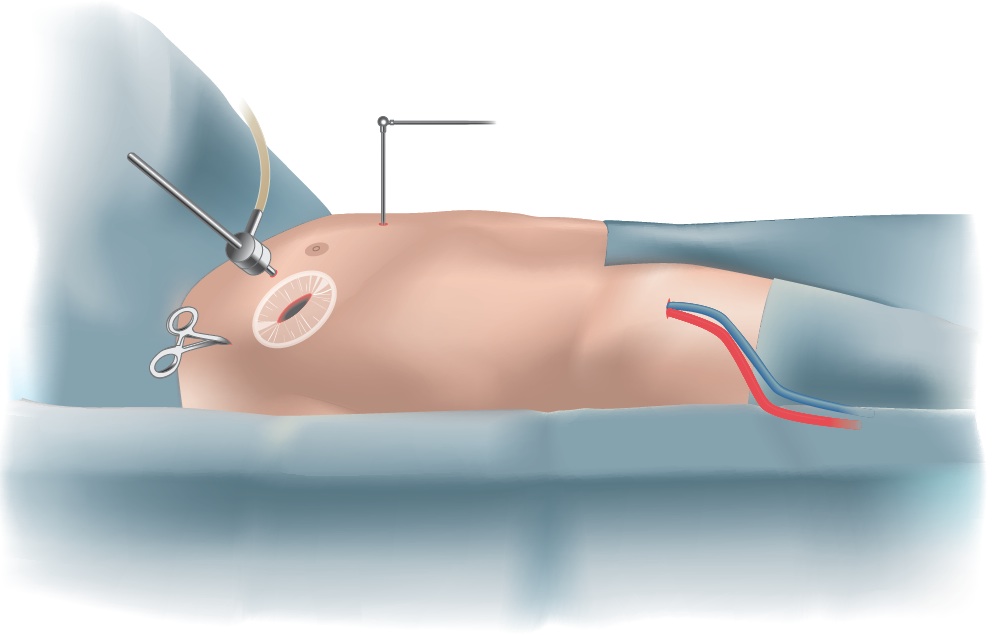

The surgery is performed through the small space between the ribs. The heart-lung machine is inserted via a small incision in the groin, allowing the heart to be stopped during repair of the valve. A soft retractor is inserted, which gently opens the narrow space between the ribs, enabling the surgeon to insert the specialized minimally invasive instruments. An endoscope, ideally with a 3D camera, is inserted that will provide a high-resolution image of the mitral valve.

| Surgical Setup for Minimally Invasive Mitral Valve Surgery |